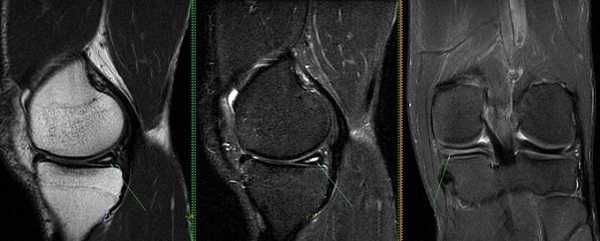

МРТ переднего рога медиального мениска коленного сустава

Повреждение медиального хряща на снимке МРТ

Разрыв заднего рога медиального мениска на снимке МРТ

Признаком повреждения мениска служит наличие линейного гиперинтенсивного очага на Т2-взвешенных изображениях. Участок сообщается с суставной поверхностью хряща, линию разрыва прослеживают на двух и более сканируемых срезах. При этом наблюдают деформацию и фрагментацию пластины.

Томограмма коленного сустава при радиальном разрыве мениска (указан стрелкой)

В зависимости от степени повреждения на снимках МРТ в режиме Т2 видны:

- очаг повышения интенсивности сигнала шаровидной формы, не связанный с поверхностью мениска (I стадия);

- светлый участок линейной формы, не затрагивающий хрящевой край (II стадия);

- повышение интенсивности сигнала распространяется на одну (III a) или обе (III b стадия) суставные поверхности пластины.

Разрыв заднего рога медиального хряща на снимках, выполненных в разных режимах, стрелка указывает на нарушение целостности пластины